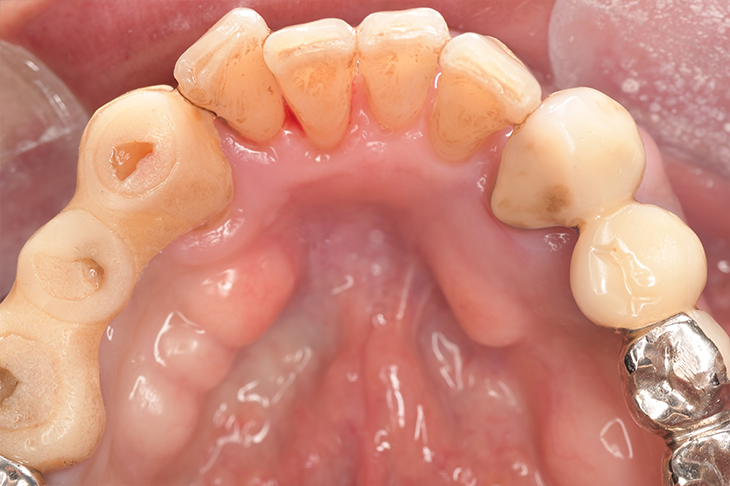

クリーニングの症例

現在の治療費と異なる場合がございます。最新の治療費は料金表をご確認ください。CASE 1

Before

After

基本情報

| 主訴 | 見た目をきれいにしたい |

| 治療期間 | 6ヶ月 |

| 治療費 | ジルコニアボンド(セラミックの被せもの)¥165,000×7(税込み) オフィスホワイトニング4回 ¥4,400×4(税込み) ホームホワイトニング¥11,000 |

| リスク・副作用 | かみ合わせがとても強い方の場合、稀に割れてしまうことがあります。 |

| 先生からの提案 | 上の前歯6本と右下の2番目の歯はセラミックの被せもので治療。 残りの下の前歯5本はプラスチックの材料で虫歯を治療し、 ホワイトニングをおこないました。白くなったご自身の歯の色に合わせてセラミックの 被せものを作成しています。 模型上で完成後をシュミレーションし、上の歯茎の位置をきれいに見えるように 揃えています。(外科処置はしていません) |